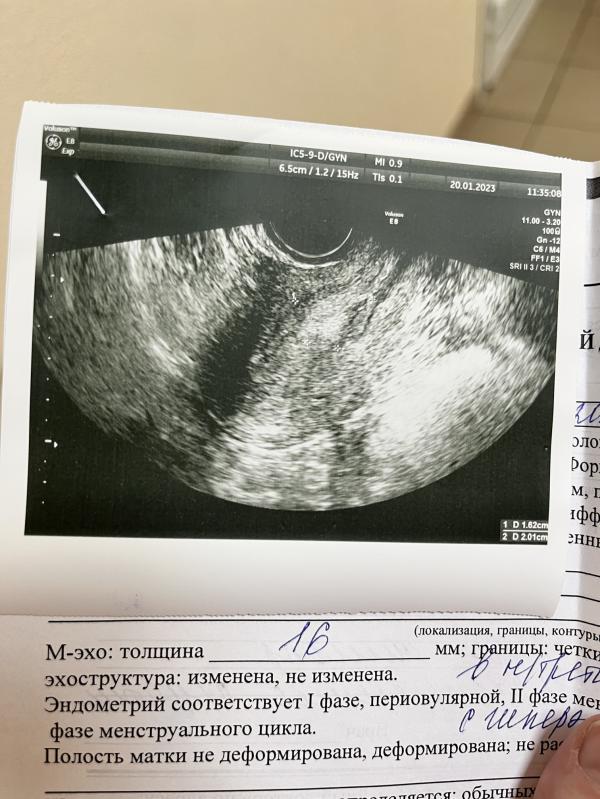

Мы с мужем планировали скорую вторую беременность, с третьего раза все сложилось и тест показал заветные две полоски, радости нет предела! Вчера вечером обсуждали имена, думали как через 8 месяцев будем держать нашу крохотную лялю у нас на руках. Сегодня с утра я проснулась с ощущением что ко мне приходил во сне малыш, именно мой малыш, я не помню свой сон, я редко их запоминаю если честно, но точно помню как я проснулась в прекрасном настроение с мыслью о предстоящем пополнение. Рядом уже не спала дочка, сквозь шторы проглядывали яркие лучи света, было 10:30. Мы немного валялись, как вдруг я почувствовала резкую боль перетекающую волной от диафрагмы до попы, она обездвижила меня на секунд 5, а отпустив я почувствовала что что-то стало вытекать из меня. Направившись в туалет более ясно не стало, трусы темные, но на бумаге я увидела светло-коричневые выделения. Время 11:05 Написав в чат беременных девушек и подруге было ясно что надо двигать в сторону узи или вызывать скорую. Звоню в платку, время на 11:30. Быстро вызываю такси, одеваемся с дочкой, начинаем выходить и понимаю что вызвала не по детскому тарифу.. Слезно уговариваю таксиста отвезти нас (у нас в городе очень принципиальны на счет кресел), он нас берет, едем. Понимаю что нет банковской карты, муж на работе и связи с ним нет. Стараюсь сохранить спокойствие. Приехали, третий этаж, лифт сломан. Беру свое 12ти килограммовое дитя, поднимаемся. Понимаю что я уже вся в крови, все липко и влажно, я в одной ежедневке. Осмотр, ужасно больно, узи - остатки хориона виднеются, сохранять уже нечего. Выписали таблетки, сказали через 10 дней проверить все ли вышло. Оплатила по спб 2900₽ чтобы услышать что у меня самопроизвольный выкидыш, мило. Я не плакала, не до конца понимала что это происходит именно сейчас и именно со мной. Вернулись домой, муж уже дома, рассказала новость и ушла в душ отмываться и дать мужу тоже переварить, что малыш решил нас покинуть. Включила воду, села под струю горячей воды и начала реветь взахлеб, наверное только тогда пришло осознание утраты. 4 недели я уже жила беременной вторым ребенком, 4 недели он был в моем животике и развивался. Но что-то случилось и он не прижился, не справился, не развился должным образом, не прошел естественный отбор. Мысль о том, что его сердечко могло уже стучать просто разрывало меня изнутри. Выйдя из душа мне стало чуть легче, после того как муж принёс лекарство и вкусняшки, мы поели, выпили кофе, поговорили и пришло принятие, что все так как должно быть. Поняли, что если бы не малыш завтра мы не поехали бы за новой машиной и что жизнь была бы чуть другой. За эти 4 недели, как мы узнали что будет малыш многое поменялось, за что мы ему очень благодарны. Часа в 4 вечера мы шли к моим родителям в гости и по дороге я почувствовала что из меня что-то вывалилось. Когда мы дошли, я зашла в туалет и на прокладке увидела сгусток длиной с мизинец, там были жилки, трубки и было очевидно что это сам малыш. Зрелище если честно отвратительное. Я позвала мужа, показала ему нашего ребенка. Он не оценил, ещё бы. Но мне было тяжело переживать это одной, хотелось чтобы он тоже проникся как это страшно. Мы вместе смыли то что осталось от ребенка и чуть помолчали. Родители не знали что я беременна, да и дома их ещё не было. Рассказывать мы не собираемся. После того как вышел сгусток выделения сошли на нет, очень мало, почти закончились.